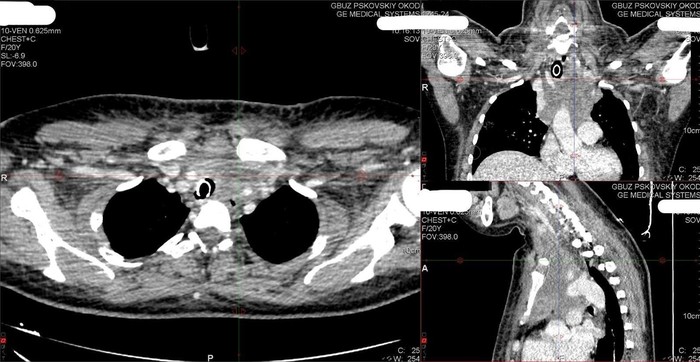

В Псковский областной клинический онкологический диспансер обратилась 21-летняя пациентка в тяжёлом состоянии с жалобами на затрудненное дыхание и одутловатость лица. Причиной стало опухолевое поражение лимфоузлов средостения, которые, превратившись в большой конгломерат с кулак, сдавили трахею пациентки и верхнюю полую вену – очень важный крупный сосуд в грудной клетке. Об этом Интернет-порталу ВЛуки.ру рассказали в пресс-службе Комитета по здравоохранению Псковской области.

Пациентке нужно было провести биопсию, так как назначить специфическое лечение возможно только после гистологического подтверждения диагноза злокачественной опухоли. Но опухоль располагалась в очень сложном для доступа и опасном месте – в грудной клетке, в средостении, охватывая жизненно важные органы.

Пациентке была выполнена биопсия опухоли через минидоступ (процедура Чемберлена) и в скорейшие сроки проведено исследование опухоли. Благодаря уровню и квалификации всех служб Псковского онкодиспансера удалось быстро и точно установить диагноз - лимфома.